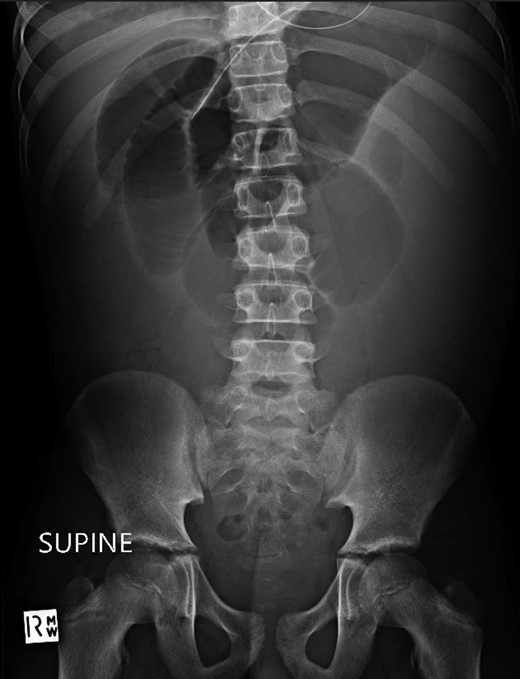

A 10-year-old boy presented unwell with generalized peritonitis after 3 days of abdominal pain, nausea and anorexia. He had a low-grade fever but all other vitals were within normal limits. Blood tests showed a raised white cell count of 16 × 109 with neutrophilia and raised C-Reactive Protein of 127 mg/l. Laparoscopy revealed generalized purulent peritonitis secondary to perforated appendicitis. Appendicectomy was performed and the appendiceal stump was secured. Lavage of the abdomen was performed with a minimum of four litres of warmed normal saline. Fluid was suctioned, an abdominal drain was placed and the pneumoperitoneum was deflated. By the second postoperative day, he developed an ileus with persistent vomiting (Fig. 1). This was managed conservatively with nasogastric intubation, bowel rest, electrolyte replacement and fluid therapy. It became clear by the fifth postoperative day that the patient had intestinal obstruction. On examination, he had a distended abdomen, with intractable nausea and vomiting. Blood tests revealed a normal white cell count and potassium remained at 3.3 despite supplemental intravenous replacement. Abdominal X-ray revealed a small bowel obstruction and he was taken back to theatre for an emergency laparotomy (Figs 2 and 3). A small bowel volvulus was discovered, with no evidence of intestinal malrotation. The volvulus involved a segment of distal jejunum to proximal ileum causing complete small bowel obstruction.

Erect chest radiograph on day 5 more consistent with small bowel obstruction.

Supine abdominal radiograph on day 5 showing dilated small bowel loops with no bowel gas evident in the colon.